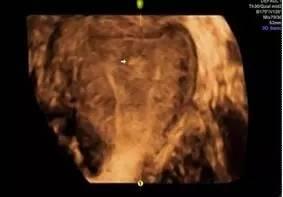

图:三维超声下的宫腔粘连